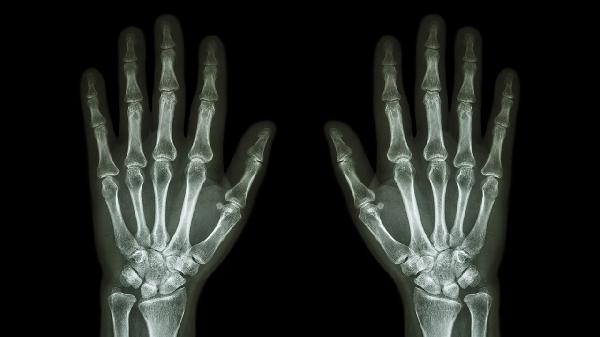

骨折手术后三个月骨头没长是什么原因

骨折手术后三个月骨头没长可能与固定不牢固、营养不良、感染、局部血供不足或骨质疏松等因素有关。建议及时就医复查,明确具体原因后针对性处理。

骨折内固定物松动或外固定支架移位可能导致骨端不稳定。骨折端异常活动会干扰骨痂形成,表现为局部肿胀疼痛,X线显示骨折线清晰。需通过影像学评估固定状态,必要时调整固定方式或二次手术加固。

绝经后女性或长期使用糖皮质激素者骨密度降低,成骨能力下降。双能X线吸收检测仪显示T值低于-2.5,可遵医嘱使用阿仑膦酸钠维D3片、鲑降钙素鼻喷剂等抗骨质疏松药物。

术后三个月未愈合需复查X线或CT评估骨痂生长情况,避免患肢过早负重。保持均衡饮食,每日摄入300毫升牛奶、50克瘦肉及深绿色蔬菜。在医生指导下进行肌肉等长收缩训练,定期监测血清钙磷及碱性磷酸酶水平。吸烟者需严格戒烟,糖尿病患控制血糖在稳定范围。